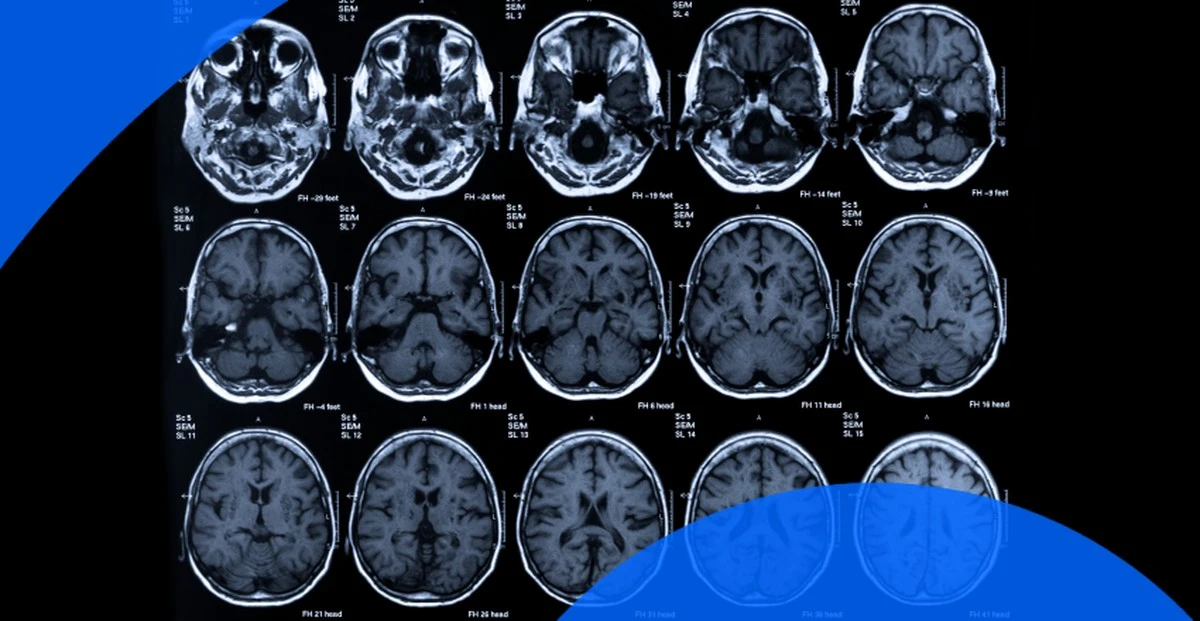

Badanie, które zobaczyłem, opierało się na funkcjonalnym rezonansie magnetycznym. Obserwowano przepływ krwi w mózgach osób pijących regularnie ponad 400 mg kofeiny dziennie – czyli około czterech standardowych kaw. Wyniki były bezlitosne: u tych osób dochodziło do widocznego zmniejszenia przepływu krwi w korze przedczołowej.

To właśnie ten obszar odpowiada za nasze planowanie, podejmowanie decyzji i pamięć operacyjną. Kofeina oszukuje twój mózg, blokując receptory adenozyny, która wysyła sygnał o zmęczeniu. Kiedy ciągle blokujesz ten komunikat, mózg przechodzi w tryb hiperaktywności, który na dłuższą metę jest nie do utrzymania.